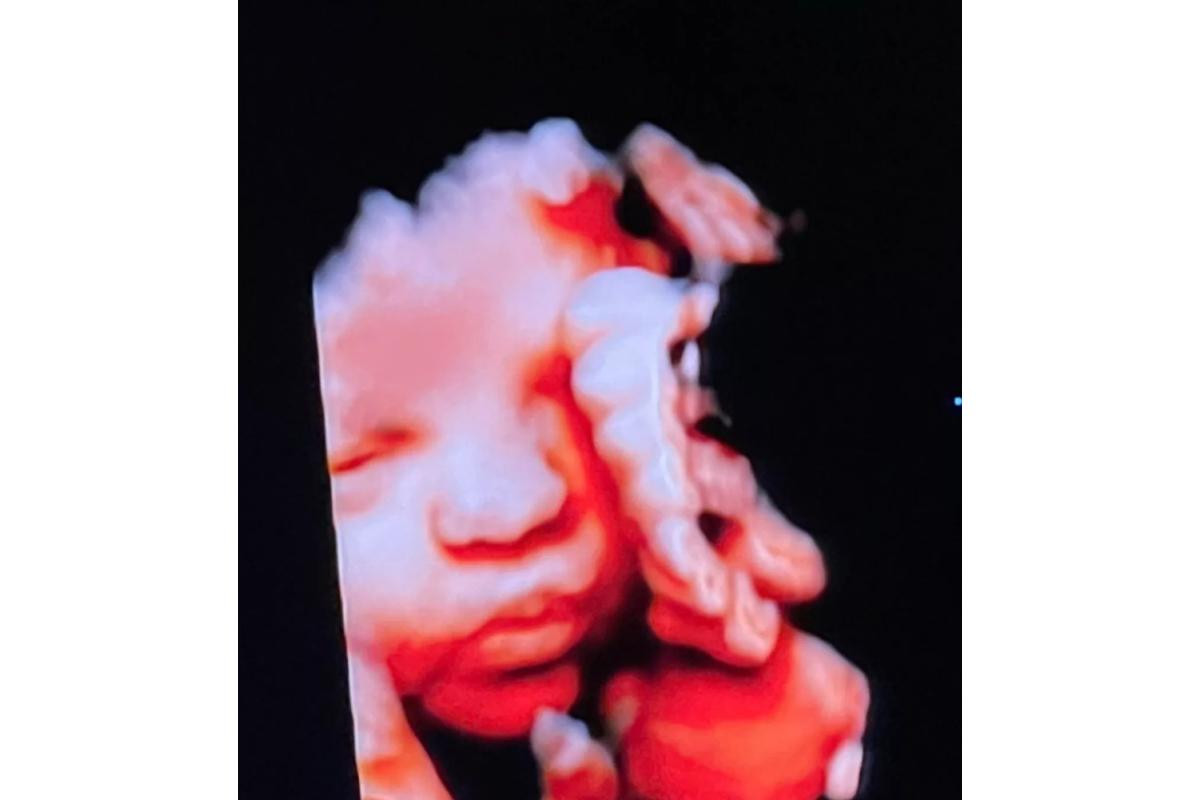

Bárbara Evans usou as redes sociais neste sábado, 26 de março, para compartilhar o ultrassom registrado durante sua última visita ao médico.

Bárbara ainda mostrou que a filha já tem bastante cabelo. “Ela é cabeluda”, entregou a influenciadora ao postar outra imagem com detalhes.